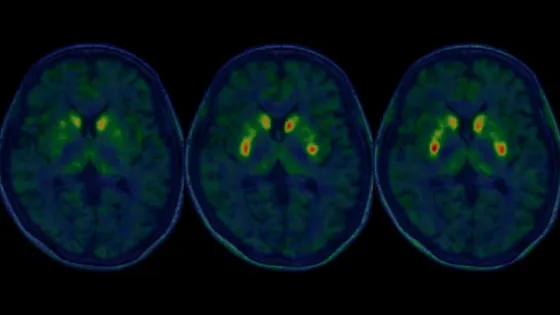

Обложка: Изображение из статьи. Nobukatsu Sawamoto et al. / Nature, 2025